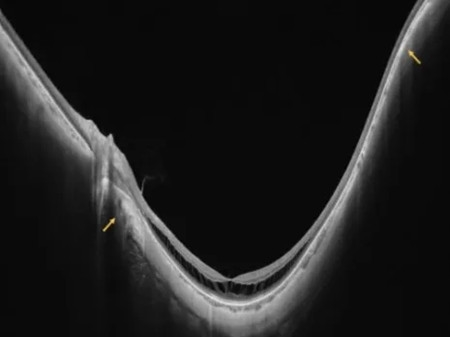

如黄斑萎缩、黄斑裂孔、黄斑出血、黄斑劈裂等并发症。

黄斑劈裂

黄斑裂孔